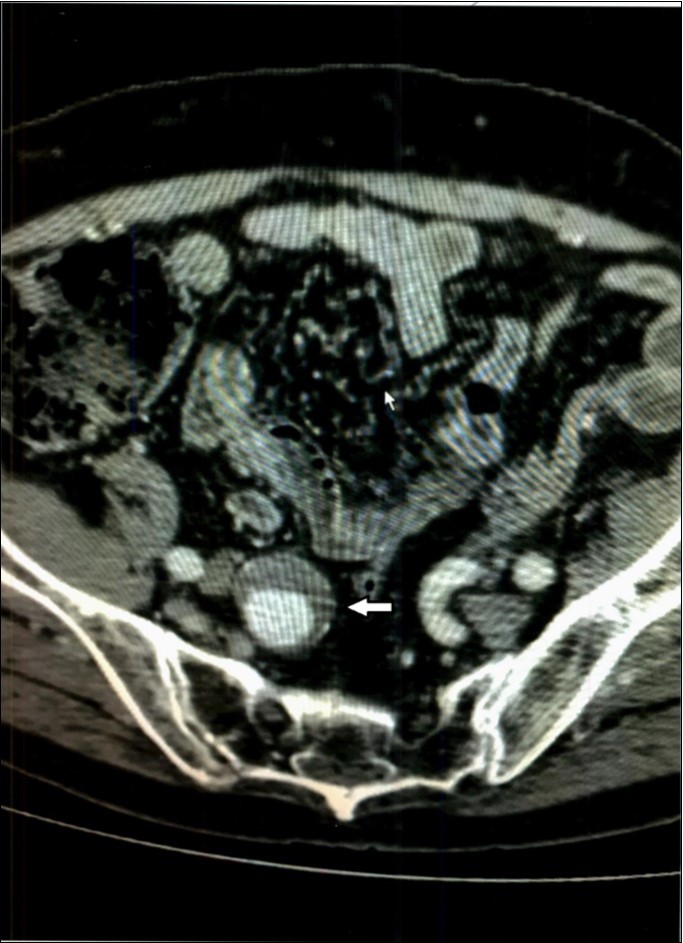

Complete metabolic panel was normal with normal hemogram. Immediate computed tomography (CT scan) revealed a 1.5 x 2 centimeter mesenteric aneurysm, possibly ruptured, Figure 2, as well as two smaller aneurysms a few millimeters each in diameter and abdominal aortic and carotid dilatation. A few small galls stones were seen. Immediate percutaneous embolization of the large aneurysm was performed two days before the procedure and six days afterward he received Levaquin. Follow up CT scan of the abdomen 18 months later showed the embolized mesenteric aneurysm and no change in the smaller ones. The symptoms have not recurred two years later.

Figure 2.Case 2 – Superior Mesenteric Artery Branch Aneurysm.

In our second patient, Case 2, in addition to the aneurysm, the CT scan indicated “probable” bleeding, Figure 2, without any sign of systemic bleeding or infection, clinically or in the hemogram. The blood cultures were normal six days after treatment. White blood cell counts were normal and only mild anemia was present. Therefore, it is doubtful the aneurysm was mycotic. The “halo” around the aneurysm can be interpreted as pressure effect of the enlarging aneurysm on the surrounding tissues.